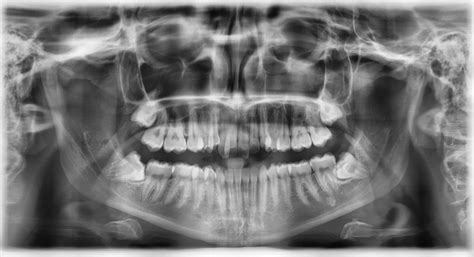

- Panoramatické röntgenové snímky: Tento typ zachytáva široký pohľad na celé ústa vrátane všetkých zubov, čeľuste a okolitých kostných štruktúr.

- Hodnotenie čeľuste a prínosových dutín: Panoramatické röntgenové snímky poskytujú prehľad o čeľusti a okolitých štruktúrach vrátane prinosových dutín.